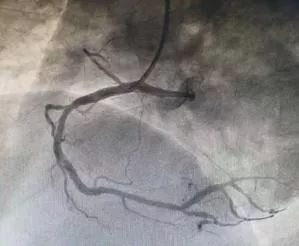

术后

患者由心血管科迅速转运至介入诊疗室,田军主任医师和徐林东副主任医师在局麻下,经右侧桡动脉穿刺行冠脉造影检查发现:患者右冠状动脉远段完全闭塞,血流完全中断,必须行PCI治疗开通闭塞血管。迅速将病情告知家属并再次征得同意后,紧急行右冠状动脉远段球囊扩张术及支架置入术。在为患者成功置入一枚支架后,造影显示支架膨胀良好,血管狭窄消失,血流恢复正常,患者胸痛症状完全消失,转危为安。